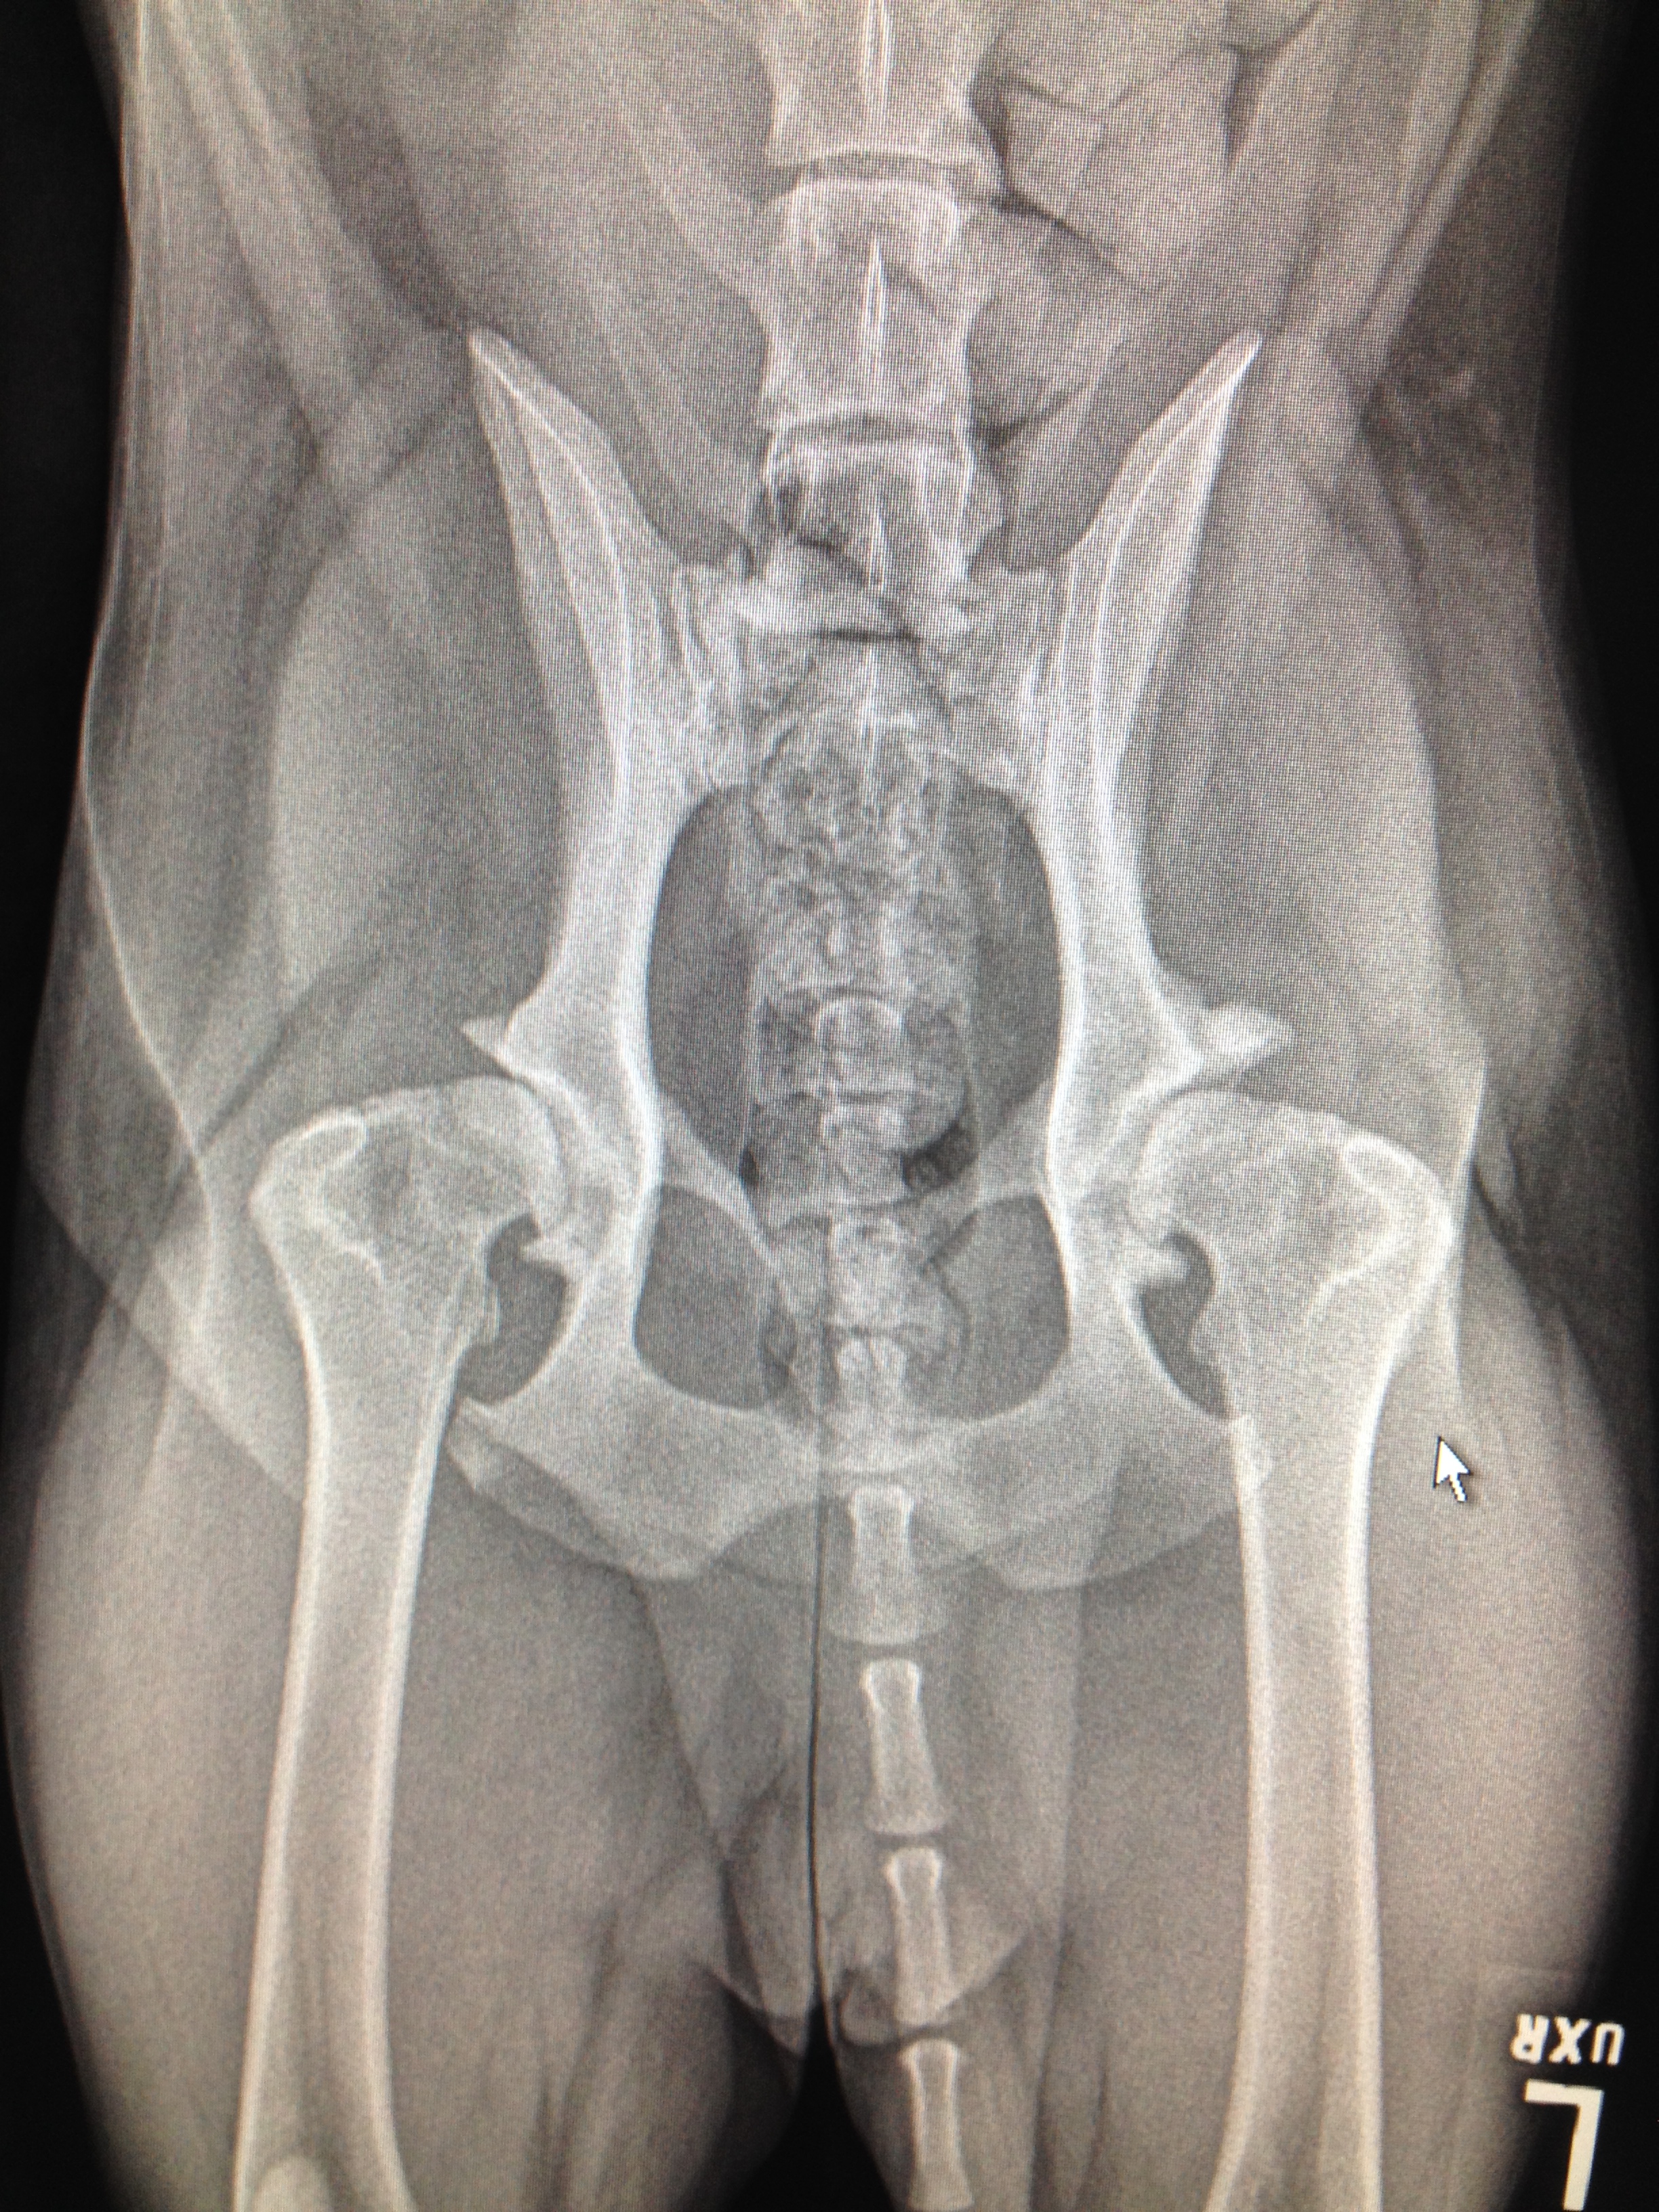

Voici des hanches d’un chien dysplasique. L’ostéoarthrose a envahit les hanches. On voit facilement que la tête fémorale est déformée par du remodelage osseux de l’articulation qui tente en vain de se stabiliser pour se protéger.